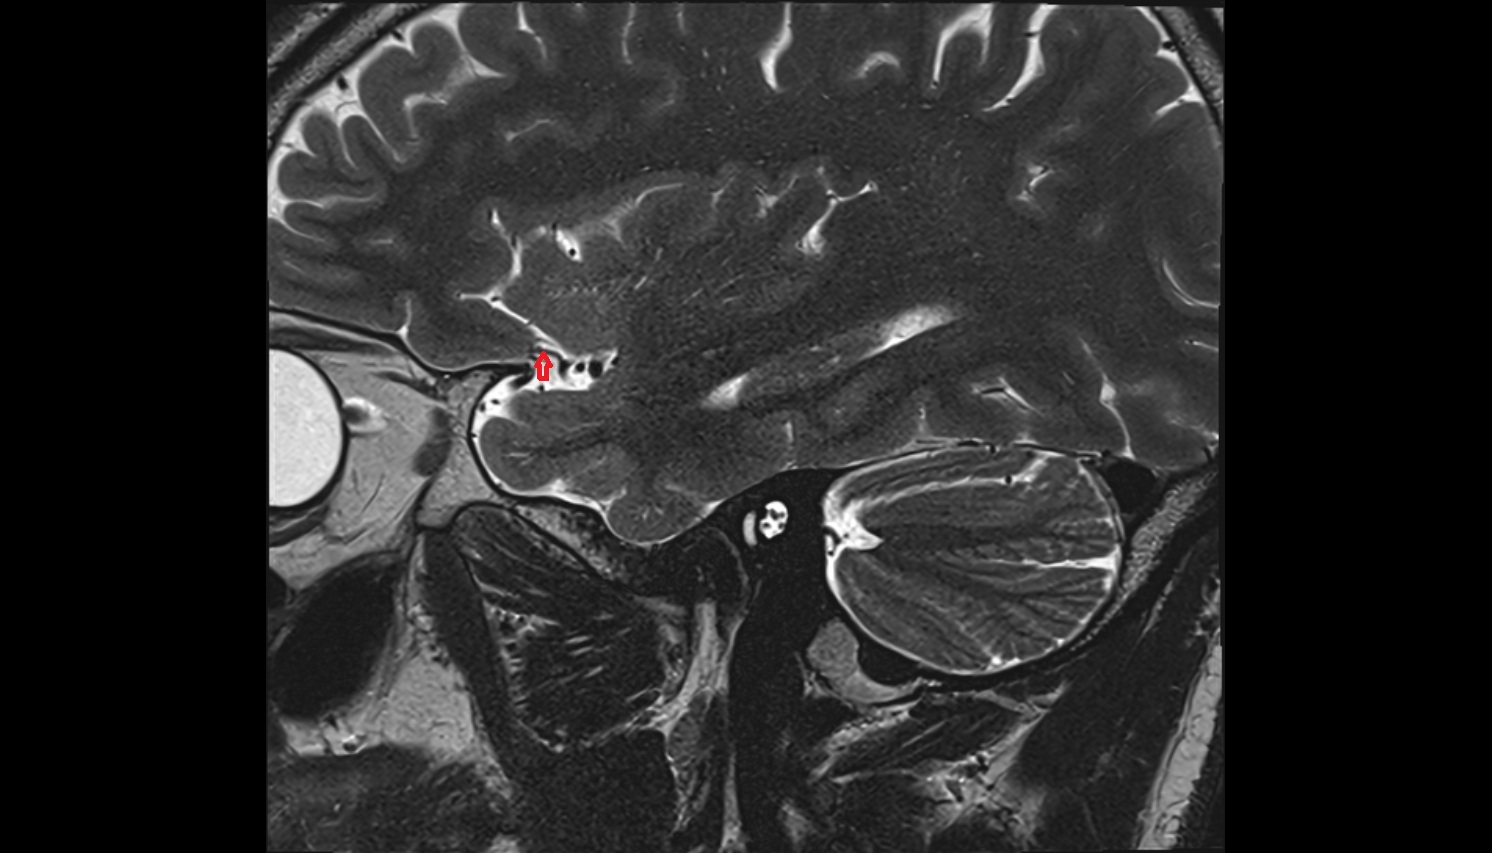

- Temporomandibular joint

- Mandibular condyle

- Mandibular fossa